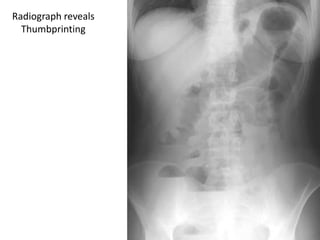

Plain Abdominal X-ray:

Thumbprinting appearance Thickening of the colonic wall + bowel

wall edema.

• Colonic segmental dilatation exceeding 5 cm with an irregular edge

outlined by gas, correlates strongly with ulceration.

• In toxic megacolon, the bowel is dilated with loss of haustral

markings.

Radiograph reveals

Thumbprinting